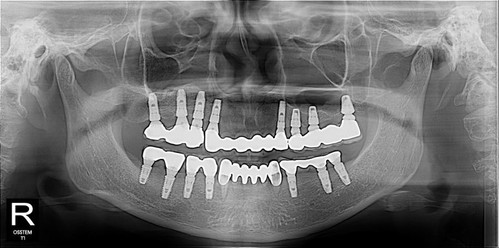

마지막 남은 두 개의 치아... 흔들리고 아팠지만 임플란트 수술이 너무 겁나서 참다가 참다가 딸이 데리고 오신 환자분

근데 다른 이는 다 임플란트라서 선택지가 없다.

뽑고 임플란트가 최선일 것 같습니다..